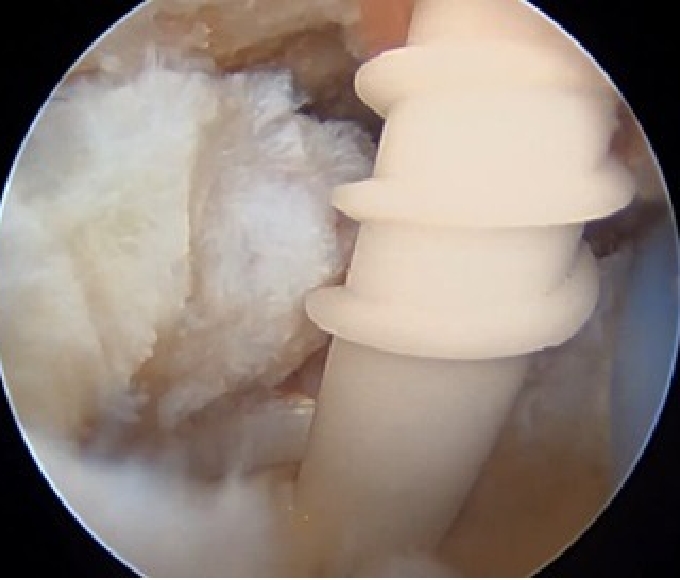

③腱板縫合

U字型の中断裂

上腕骨頭(大結節Footprint)が露出してしまっている。